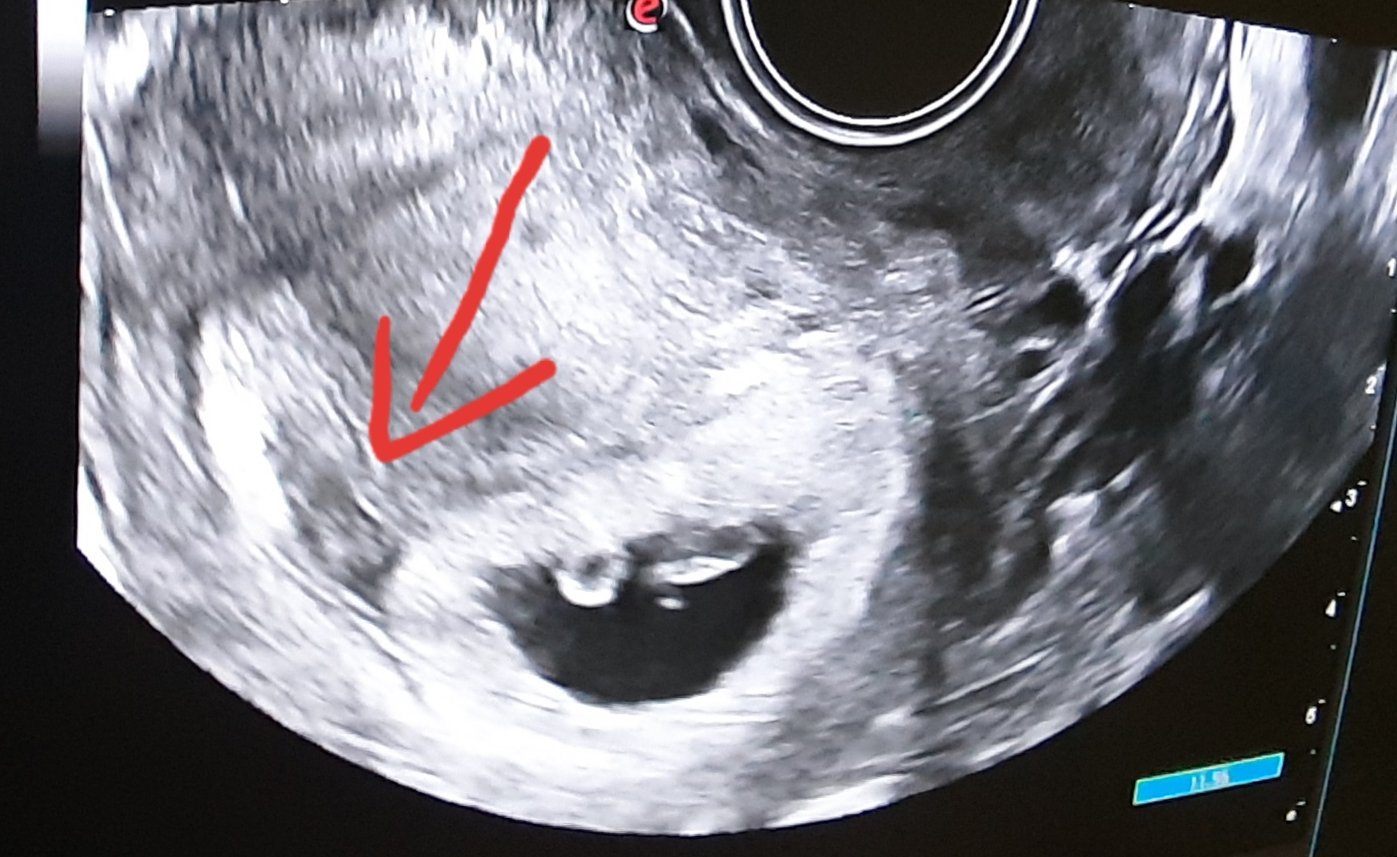

chcela by som sa poradiť ohľadom mojej situácie. Bola som na usg v 7. týždni + 2 dni. Pýtala som sa doktorky, že či to môžu byť dvojičky a ona povedala, že uvidíme pri kontrole.

Na kontrolu idem v 10. týždni + 4 dni. Ale na fotke zo sona je čosi vidno. Nie je to ani hematóm,cysta a ani nádor.

Môže to byť dvojička?